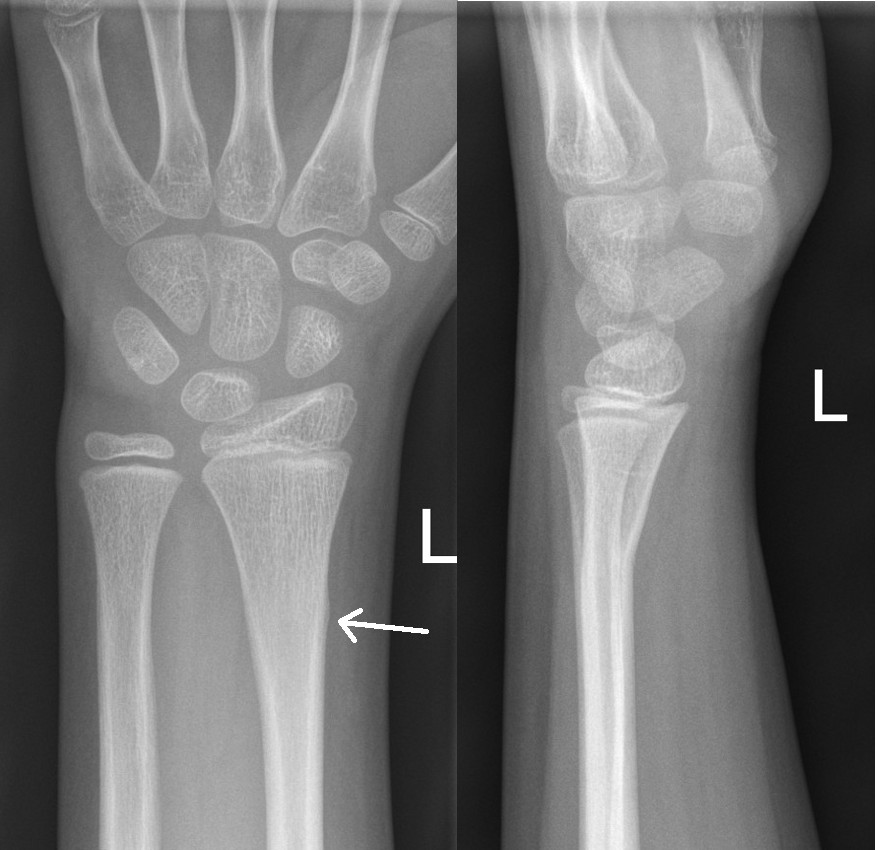

A: Undisplaced distal scaphoid fracture

B: Sclerotic line in follow up X-ray 2 weeks later